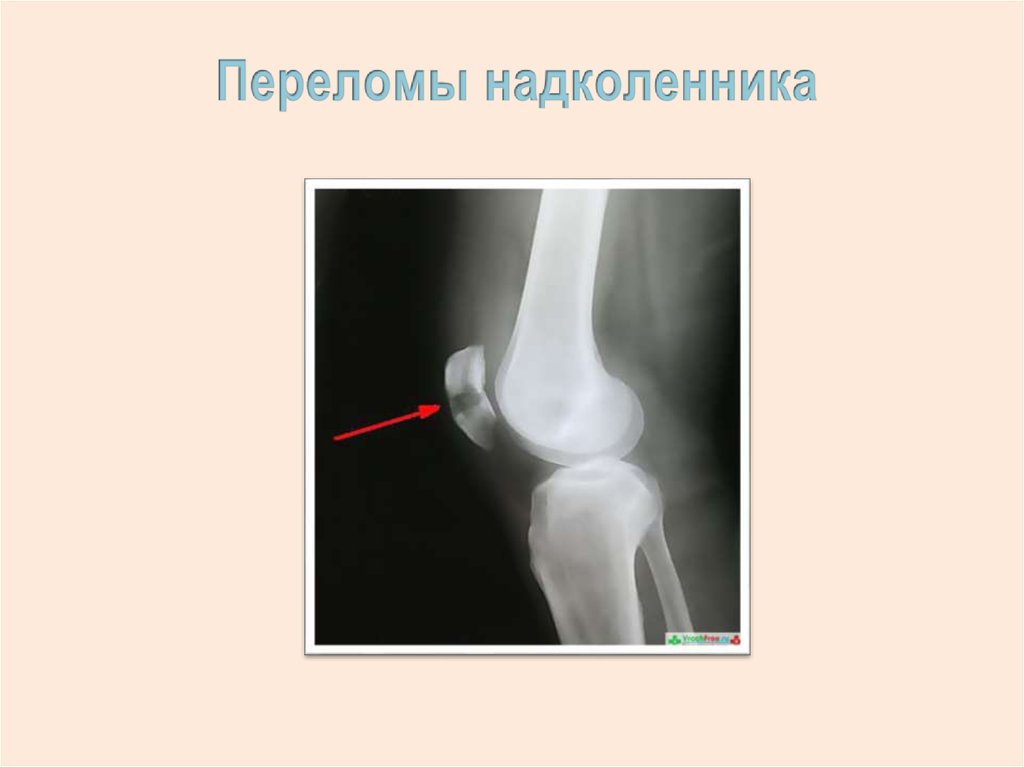

18.

19.

20.